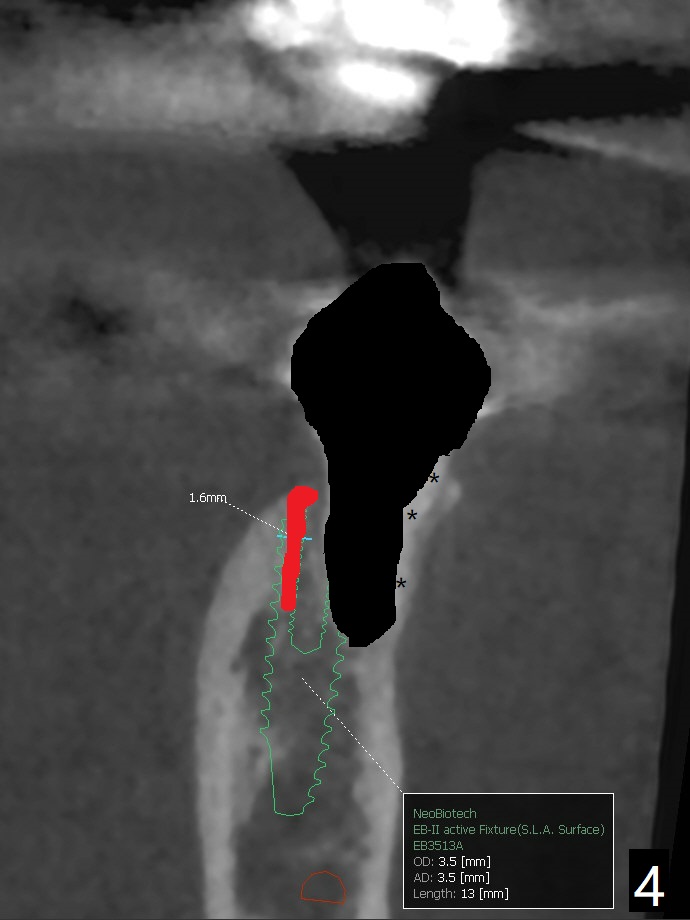

A 53-year-old woman develops an abscess lingual to the tooth #20 before #19 final restoration. Reanalysis of CT taken 5 months earlier shows the thin buccal plate (Fig.1 B). A 3.5x13 mm bone-level/3.5x17 mm tissue-level implant should be lingually placed (Fig.2,3). Socket shield will be performed (Fig.4 *); the lingual cortex removed with Lindamann bur (red) for ~1.6 mm. Initial osteotomy will be conducted in the lingual wall of the socket coronally (Fig.5 white arrow); after penetration, the initial drill will change the trajectory (Fig.6).